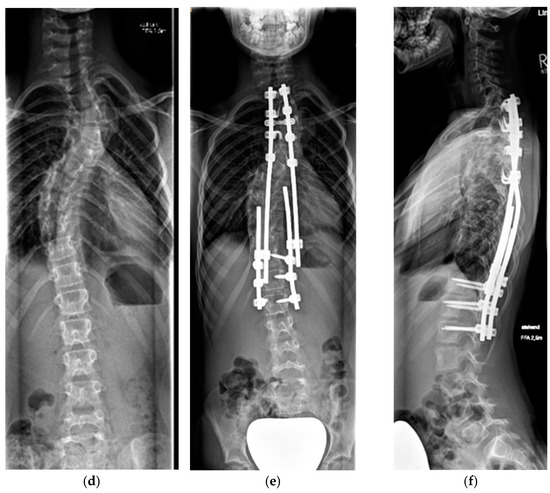

4.2.2. Adolescent Spinal Deformity

5.2.2. Definitive Spinal Fusion

| Fusion | 13.4 (±2.3) | 3.1 (±1.7) | 66 (±13.6) | 26 (±11.3) | 66 (±23.7) |